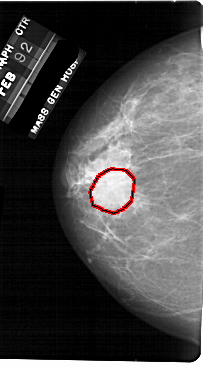

A_1710_1.LEFT_CC

LEFT_CC LINES 5491 PIXELS_PER_LINE 3031 BITS_PER_PIXEL 12 RESOLUTION 43.5 OVERLAY

FILE: A_1710_1.LEFT_CC.OVERLAY

TOTAL_ABNORMALITIES 1

ABNORMALITY 1

LESION_TYPE MASS SHAPE ROUND MARGINS OBSCURED

ASSESSMENT 3

SUBTLETY 5

PATHOLOGY BENIGN

TOTAL_OUTLINES 1

BOUNDARY